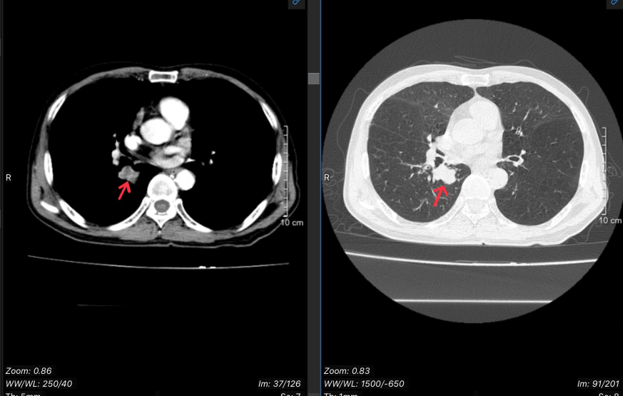

- CT lồng ngực:

Hình 1: Hình ảnh chụp cắt lớp vi tính lồng ngực cho thấy nhu mô thùy dưới phổi có khối kích thước 26x20mm, bờ không đều, sau tiêm ngấm thuốc. Hạch trung thất. Giãn phế nang hai phổi. Dải xẹp mành nhu mô thùy giữa phổi phải